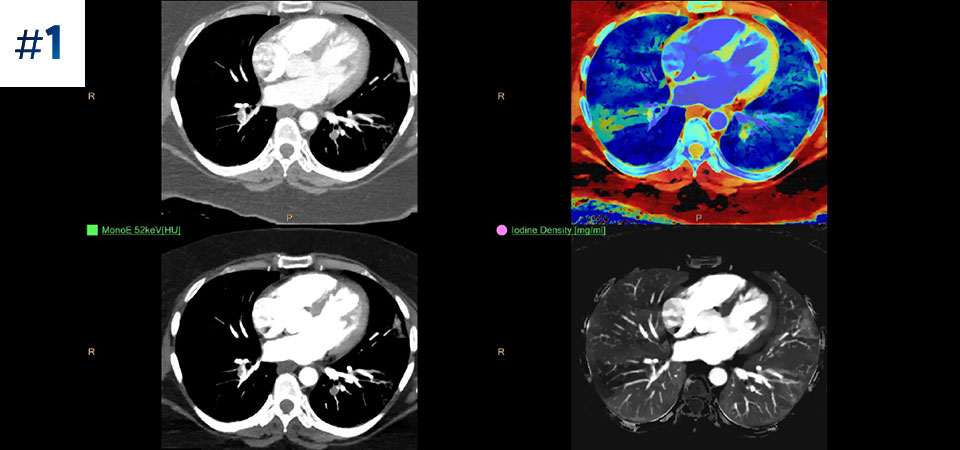

Vai oltre la TC convenzionale. Scopri come i risultati con diversi strati del detettore spettrale possono migliorare l'affidabilità diagnostica.

Osserva la differenza tra la TC basata su detettore spettrale e la TC convenzionale